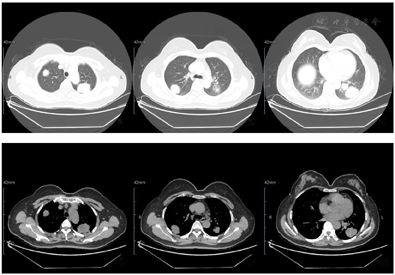

入院前查下肢彩超示:左股骨中下段骨皮质浅方实性占位。入院后查左股骨全长正侧位片示:左股骨中段骨质密度稍显减低,骨皮质毛糙、变薄,周围软组织肿胀,关节对应关系良好。查肌骨超声所见图1:左侧股骨中下段骨长轴纵切面骨皮质局部骨膜增厚,不规则隆起,可探及范围约157 mm×17 mm混合回声区,后方回声减低,交界处的骨膜回声增强、增厚、抬高呈"Codman"三角征;围绕骨干横切面见"轮辐样"放射状分布的针状强回声,回声与骨皮质表面垂直;彩超多普勒血流显像(color Doppler flow imaging,CDFI):内可探及星点状血流信号;后方骨皮质尚连续,中下段边缘毛糙。进一步查左股骨中下段增强CT所见图2:左股骨中下段髓腔内见纵形软组织密度影,邻近骨皮质稍增厚且骨质密度减低,呈筛孔样骨质破坏,周围可见放射状骨膜反应及软组织肿块,骨干未见明显膨胀,增强扫描后髓腔内见穿行血管影,周围软组织肿块中度强化。查左股骨中下段核磁见图3:左股骨干中下段髓腔内条带状长T1、压脂长T2信号影,骨皮质厚薄不均,信号欠连续,压脂信号增高,骨干周围包绕软组织块,呈略短T1、压脂长T2信号影,压脂T2其内见多发细线样低信号影垂直于骨皮质分布,病变与周围软组织区界限不清,软组织内片状长T1、压脂长T2信号影;扫描所示左股骨干远端小圆形、右股骨干中段髓腔内条带状长1、压脂长T2信号影,境界较清晰,邻近骨皮质未见明确异常。查胸部CT见图4:双肺纹理增重,双肺见多发大小不等结节样高密度影,较大者边缘欠光整,呈浅分叶状,左肺下叶见索条影,纵隔内见多发小淋巴结影;肝右叶内见类圆形低密度影,边缘可见模糊稍高密度影。腹部超声所见:肝脏实质回声致密,内可见多个低回声区,较大者大小约20 mm×14 mm的肿物;脂肪肝。查腹部ECT见肝右叶上述改变外,未见其他异常。实验室化验肿瘤标志物CEA、AFP、CA-199等都在正常范围;C反应蛋白11.43 mg/L(参考范围0.00~0.60 mg/L,以下同);碱性磷酸酶183 U/L(40~150 U/L);磷酸肌酸激酶同工酶110 U/L(1~24 U/L)。